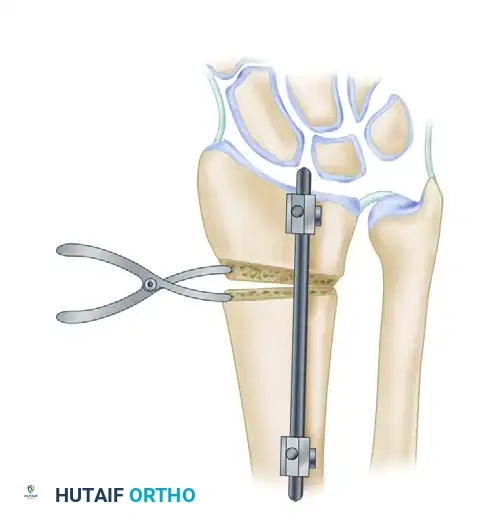

Alternative Fixation: Intramedullary Nailing

While volar plating remains the standard of care, advancements in implant technology have introduced intramedullary (IM) nail implants for the management of distal radius fractures and malunions (as described by Ilyas et al.).

IM nails offer a load-sharing construct with minimal soft-tissue disruption. However, their use in malunion correction requires precise reaming and is generally reserved for extra-articular deformities where the distal fragment is of sufficient size to accommodate the locking screws of the nail.